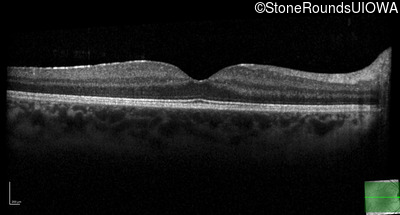

Optical Coherence Tomography - Left - 20/20 -1

Exemplar / OCT Stack